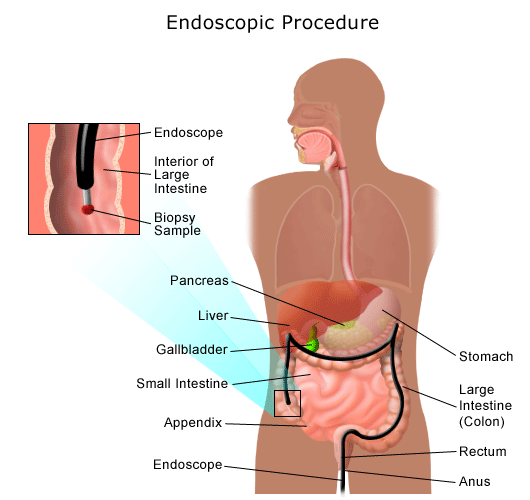

Gas in the Digestive Tract | Johns Hopkins Medicine